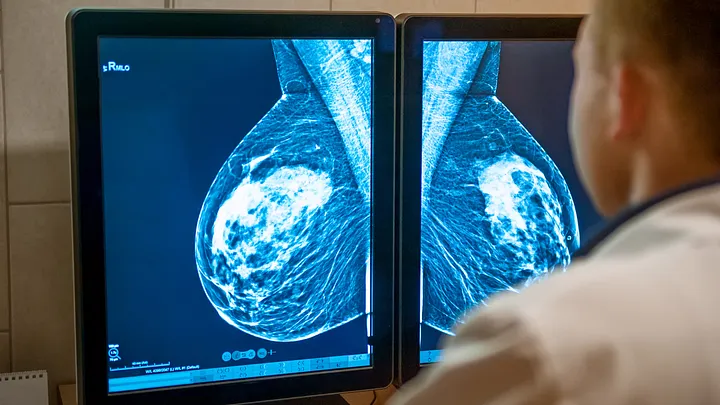

Una mastografía es un examen de rayos X especialmente diseñado para capturar imágenes detalladas del tejido mamario. Utiliza una dosis muy baja de radiación ionizante para obtener imágenes de alta resolución que pueden revelar la presencia de tumores u otras irregularidades en las mamas.

- Análisis: Las imágenes son evaluadas por un radiólogo especializado en mamografías. Este profesional busca signos de cáncer y otras anomalías.